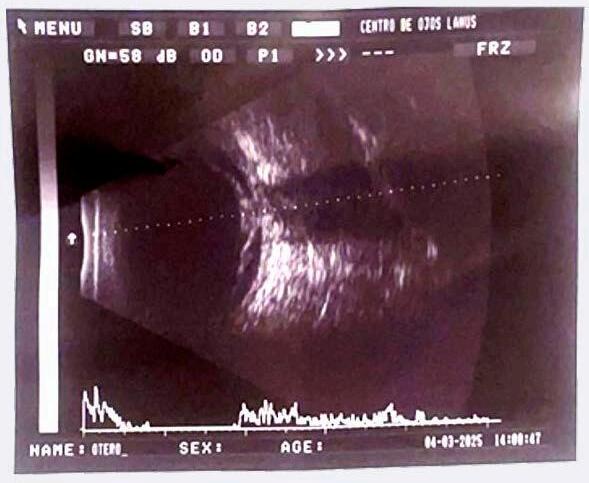

A los 45 días del inicio, el paciente refiere disminución de su agudeza visual, y presenta una AVMC de su ojo derecho de 20/200, sin afectación del ojo contralateral.

Tanto la biomicroscopía como la PIO de ambos ojos fueron sin particularidades. Al realizar el fondo de ojos del ojo derecho evidenciamos un desprendimiento de retina bulloso, mácula off , asociado a un vítreo denso. Lo registramos simultáneamente en una ecografía ocular modo A-B ( Imagen 3 ). Decidimos remitir al Servicio de retina, quienes deciden una cirugía combinada de extracción del cristalino mediante facoemulsificación y colocación de lente intraocular, junto con una vitrectomía vía pars plana (VPP) con colocación de aceite de silicon. Los controles postquirúrgicos fueron sin particularidades.

Imagen 3 - Ecografía OD